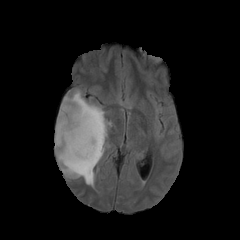

We introduce a neural network framework, utilizing adversarial learning to partition an image into two cuts, with one cut falling into a reference distribution provided by the user. This concept tackles the task of unsupervised anomaly segmentation, which has attracted increasing attention in recent years due to their broad applications in tasks with unlabelled data. This Adversarial-based Selective Cutting network (ASC-Net) bridges the two domains of cluster-based deep learning methods and adversarial-based anomaly/novelty detection algorithms. We evaluate this unsupervised learning model on BraTS brain tumor segmentation, LiTS liver lesion segmentation, and MS-SEG2015 segmentation tasks. Compared to existing methods like the AnoGAN family, our model demonstrates tremendous performance gains in unsupervised anomaly segmentation tasks. Although there is still room to further improve performance compared to supervised learning algorithms, the promising experimental results shed light on building an unsupervised learning algorithm using user-defined knowledge.